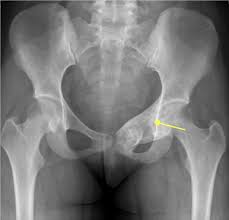

Bone cancer, also known as osteosarcoma, occurs most often in the long bones of the arms and legs. While scientists need to carry out more research into the precise cause of bone cancer, the american cancer society state that there is a range of risk factors for bone cancer, including genetics. The upper and lower leg, pelvis, upper arm, or ribs tend to be the bones affected by this. As previously mentioned, the pelvic floor is made of several layers of muscles that extend from your pubic bone to your tailbone, and has a few main functions: If a tumor spreads to the bone, it's called bone metastasis.

Metastatic Bone Disease Orthoinfo Aaos from orthoinfo.aaos.org The type of treatment used and the outlook depend on various factors including the type, site and stage of the cancer. Pelvic cancer invades the organs and structures of the pelvis, which is the cavity at the bottom of a person's trunk. During a needle biopsy, your doctor inserts a thin needle through your skin and guides it into the tumor. Suggest treatment for bone cancer. Chronic pelvic pain can result from more than one condition. In his pelvis that spread to his bones, or they were calling it bone cancer. The cause of bone cancer isn't exactly known, but there are certain factors that may contribute to or increase a person's chances of forming abnormal growths in the bone. Some people with cancer have dna mutations that they inherited from a parent.

Bladder and bowel control by emptying and holding in urges. Surgery to remove a tissue sample for testing. Primary bone cancer, cancer that begins in the bone, accounts for less than 1% of all new cancers. During a needle biopsy, your doctor inserts a thin needle through your skin and guides it into the tumor. Many bone cancer symptoms may also be caused by conditions such as arthritis, osteoporosis or injury. Causes chondrosarcoma is associated with certain genetic mutations. Infection (gastroenteritis) of the intestines can be caused by bacteria, viruses, or even parasites. Some varieties of chondrosarcoma arise from the transformation of benign cartilage lesions into cancers. The type of treatment used and the outlook depend on various factors including the type, site and stage of the cancer. Bone metastasis may be the first sign that you have cancer, or bone metastasis may occur years after cancer treatment. Pelvic pain can arise from your digestive, reproductive or urinary system. These mutations increase their risk for the disease. And a bone that breaks.

Pelvic Pain In Men 10 Most Common Causes from i0.wp.com Some people with cancer have dna mutations that they inherited from a parent. Metastatic tumors of the bones are usually osteolytic, which means that they dissolve the bone and cause multiple fractures. Persistent or unusual pain or swelling in or near a bone can be caused by cancer or by other conditions. But with treatments, it may be possible to extend your life, ease pain and other symptoms, and improve your quality of life. Treatments which may be considered include surgery, chemotherapy and radiotherapy. Cancer that has started in one place can spread to and invade other parts of the body. Cancers can be caused by dna mutations (defects) that activate oncogenes or inactivate tumor suppressor genes. This type of bone cancer usually shows up in the legs (long bones), pelvis, backbone, ribs, upper arms, and the skull.